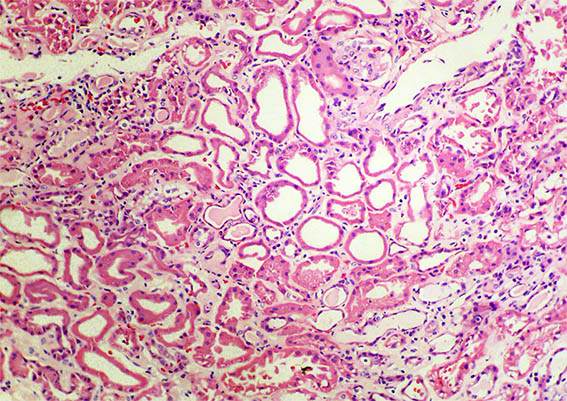

Figura 1. H&E, X200. Daño tubular agudo.